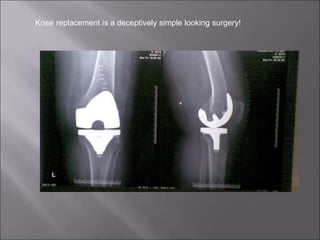

Knee replacement is a deceptively simple looking surgery!

 TKR is a soft tissue operation

 Its all about the “Balancing”!

 It is deceptively simple looking

operation